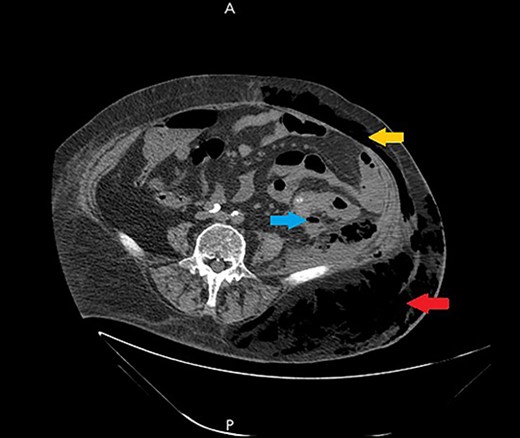

Ultrasound showed extensive subcutaneous soft tissue edema with hyperechoic areas seen in the proximal anterolateral part of the thigh. The initial diagnosis of the condition was a left iliopsoas abscess. Due to the severity of the patient’s symptoms, a non-contrast abdomen and pelvis computerized tomography (CT) scan was done (Fig. 3), which showed a large amount of subcutaneous emphysema within the left flank soft tissues that wrapped anteriorly along the left lower lateral abdominal wall with a small tract of air extending from the left retroperitoneum posterior to the left kidney and extending along the left iliopsoas muscle inferiorly. A skin defect with the underlying abscess collection and air–fluid level was noted (Fig. 4). Another CT scan section saw a soft tissue mass lesion at the distal descending colon (Fig. 5). The abscess drainage was done under CT guidance.

A non-contrast abdomen and pelvis CT scan, which shows a large amount of subcutaneous emphysema within the left flank soft tissues (lower arrow) that wrapped anteriorly along the left lower lateral abdominal wall into the anterior subcutaneous soft tissues of the left lower quadrant (upper arrow). There was also a small tract of air extending from the left retro peritoneum posterior to the left kidney and extending along the left iliopsoas muscle inferiorly (middle arrow).